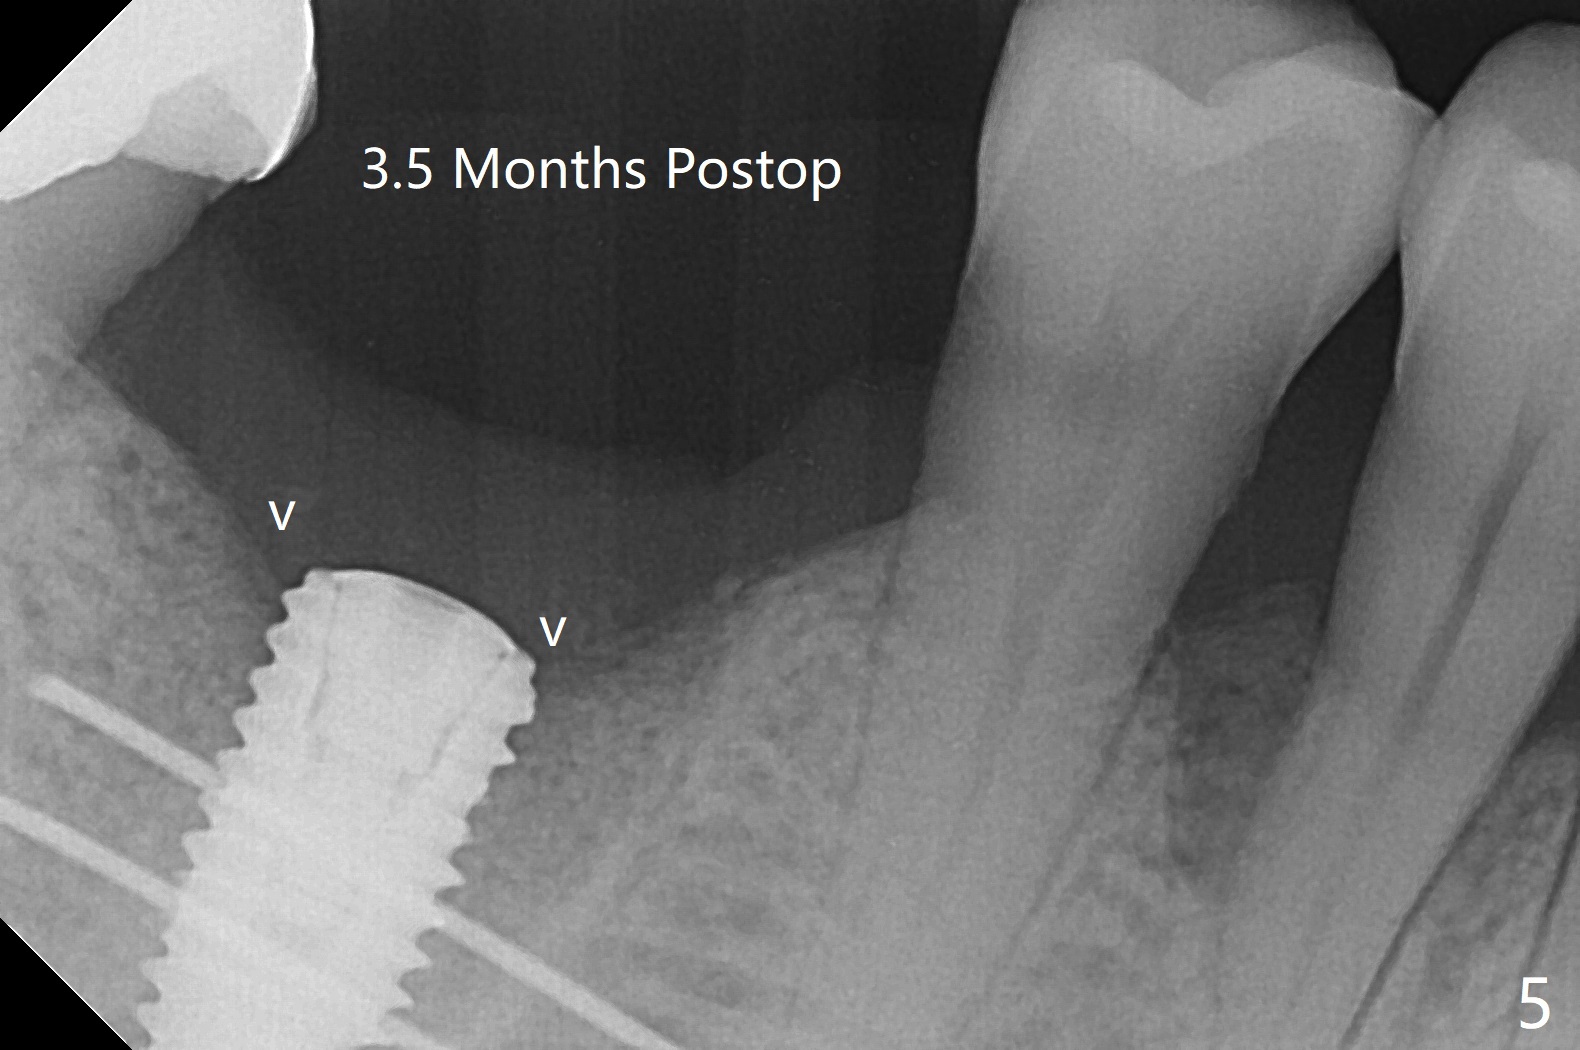

The sockets of #30 (M) of a smoker (M) are apparently not healing ~ 2 months post extraction (Fig.0, 0'). The ridge looks wide 3 months post extraction without bone graft in other office before (Fig.1) and after (Fig.2) flap surgery. The socket appears to have healed perfectly consi-dering buccal defect (M) revealed by CT ~ 1 month earlier. When a 5x10 mm implant is placed with guide and high torque (in spite of overprep), granu-lation tissue is found mesio-buccal (MB, Fig.2 *). After curettage, bone graft is placed around the implant, especially MB (Fig.3 *), followed by PRF. Periodontal dressing dislodged a few days postop because of mastication on the right side (Fig.4), whereas the anterior one (24/26) remains in place. There is a small gap around the implant when it is uncovered (Fig.5 arrowheads). It appears that some of bone graft gets lost from the incision (smoker). A 6.5x5.5(4) mm cemented abutment is seated and torqued at 30 Ncm before impression (Fig.6). There is no bone loss 11 months post cementation (Fig.7).